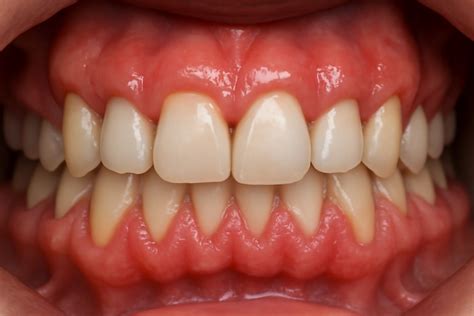

La expresión exposición gingival excesiva, comúnmente denominada sonrisa gingival, se emplea cuando durante la sonrisa se produce una sobreexposición de la encía superior. En casos severos, la sobreexposición se observa también con la boca y los labios en reposo. En general, cuanto más se exhiben los tejidos gingivales, menos estética resulta la sonrisa.

Erupción Pasiva Alterada/Retardada

La erupción pasiva es un proceso normal por el cual, después de haberse producido la erupción completa del diente, los márgenes gingivales van retrayéndose hacia apical hasta el nivel de la UAC. Cuando se produce un fracaso de la retracción de los márgenes gingivales hasta la UAC, hablamos de erupción pasiva alterada. Como los tejidos gingivales quedan posicionados coronalmente a la UAC, los dientes aparecen como cortos y cuadrados.

Esta condición puede afectar a varios dientes o a un diente aislado. La incidencia de erupción pasiva alterada en la población general es de aproximadamente el 12%. El mecanismo fisiológico de la erupción pasiva continúa incluso en la tercera década de la vida; por lo tanto, el diagnóstico de la erupción pasiva alterada debe realizarse en relación con la edad.